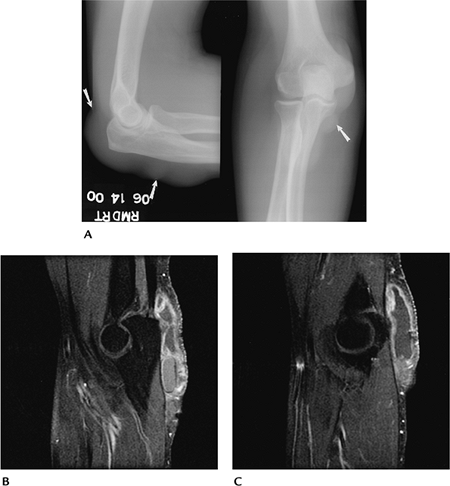

![]() |

FIGURE 8-32 Rheumatoid arthritis. AP radiograph showing joint space narrowing and erosive changes.

FIGURE 8-33 Osteoarthritis. (A) AP radiograph showing bone sclerosis and osteophytes typical of osteoarthritis. (B) Axial T2-weighted MR image showing a joint effusion with osteophytes (open arrows).

FIGURE 8-34 Gout. (A) AP and lateral radiographs demonstrate prominent nodular swelling (arrows). Sagittal (B,C)

Arthropathies

Arthropathies involving the elbow include

Routine radiographs remain the primary screening technique for detection and characterization of arthropathies.

Radionuclide scans and MRI detect changes